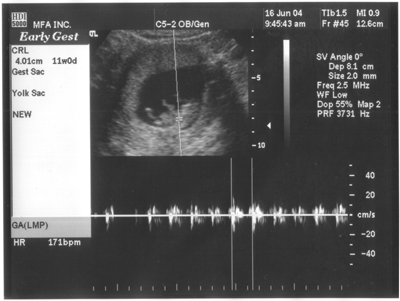

16. Juni 2004